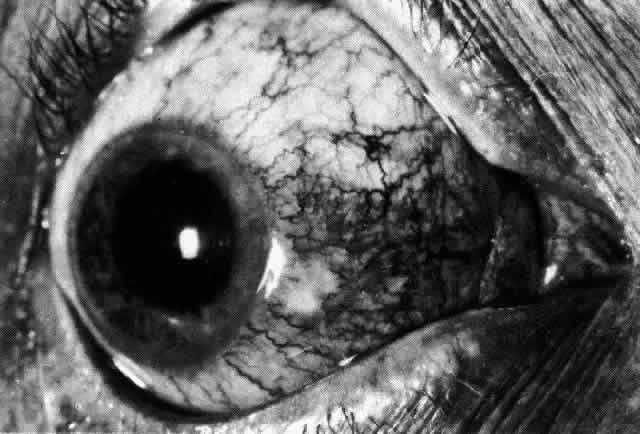

Diffuse Anterior Scleritis

Diffuse anterior scleritis is the most common and least severe type of scleritis. The inflammation is widespread, and it may involve either a small segment or the whole of the anterior segment, sometimes with such severe overlying inflammation as to justify the name “brawny” scleritis (Fig. 29). On slit lamp examination, the vascular pattern of both deep and superficial layers may be distorted, so that the normal radial pattern of the vessels is lost; large anastomotic channels develop, leading to beading and tortuosity of the remaining vessels (Figs. 30 and 31; Color Plate 1C).

Fig. 29. Intense inflammation, edema, and conjunctival chemosis that accompany acute diffuse anterior scleritis.

Fig. 30. Diffuse anterior scleritis. During the acute attack, the vessels are dilated and distorted. New vessels or large vessels not normally seen have appeared adjacent to the limbus.